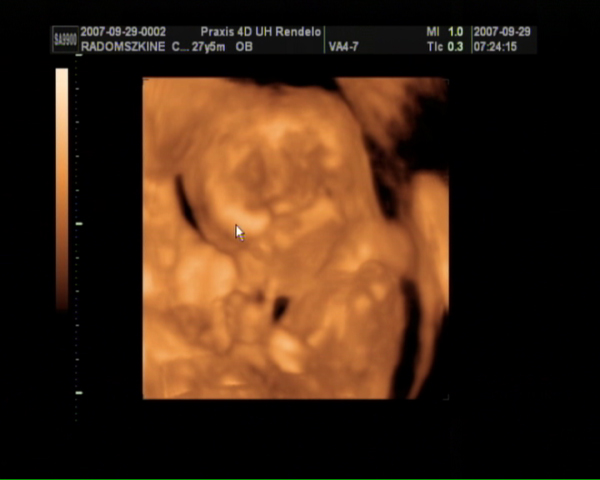

Szombaton voltunk 4D-n, tündériek a fiúk (mert kiderült, hogy 2 fiunk lesz!)! :lol:

Kép Dávid Kép Bálint